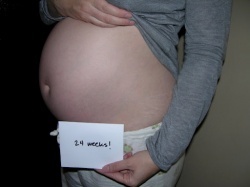

Какие есть фото УЗИ и живота на 24 неделе беременности? Какой вес и рост плода на 24 неделе беременности?

На 24 неделе беременности малыш весит чуть менее 500 г, рост его приближается к 30 сантиметрам. По размеру он похож на гроздь винограда. Все органы уже сформировались и малыш учится дышать, вдыхая околоплодные воды. При этом его альвеолы то сужаются, то расширяются. В гипофизе начинается выработка гормонов, которые в дальнейшем будут отвечать за роды у мамы.

У будущей мамы особо нет никаких забот. Токсикоз давно забыт и она наслаждается движениями малыша. Единственное, что способно испортить настроение — начинающееся искривление позвоночника из-за растущего живота.